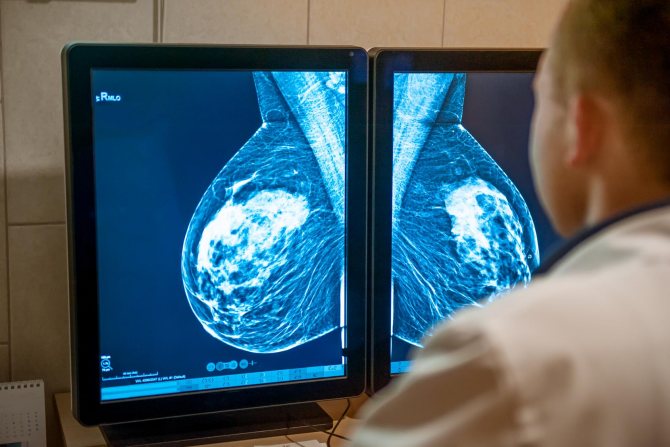

1. Маммография. Наиболее эффективный метод обнаружения бластомы молочной железы. Для получения изображения грудь зажимают между пластинами, после чего делают снимки с разных ракурсов. Здоровые ткани будут прозрачными, а уплотнения иметь четкие очертания.